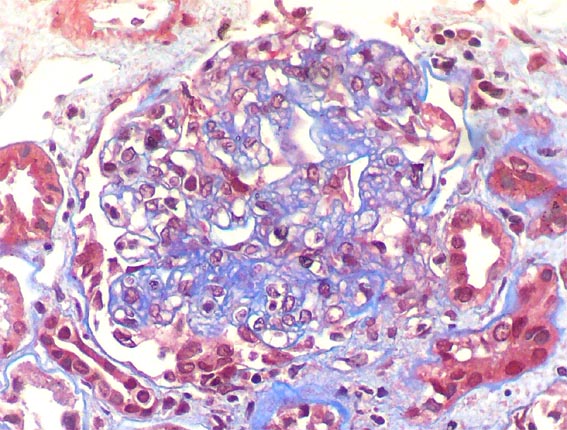

Figure 3. Masson's trichrome stain, X400.